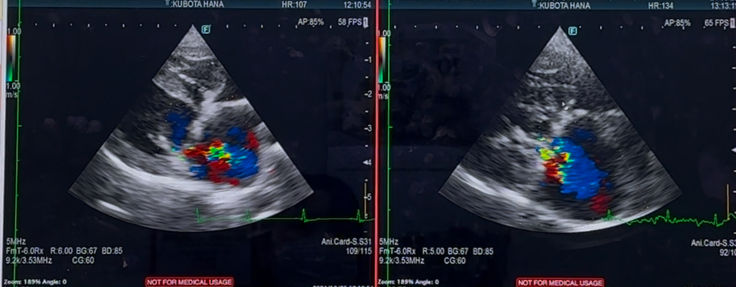

心臓の方は

逆流が残っている所は

変わらず残っているまま…

心臓の大きさも、良くも悪くも

変わりなく…

術直後から「もう少し、ちぃさくなって欲しかったのですが…」と言われており…

標準値よりは、大きいままです…

右心の三尖弁の逆流や

肺高血圧症も、悪化はなく

中等度…